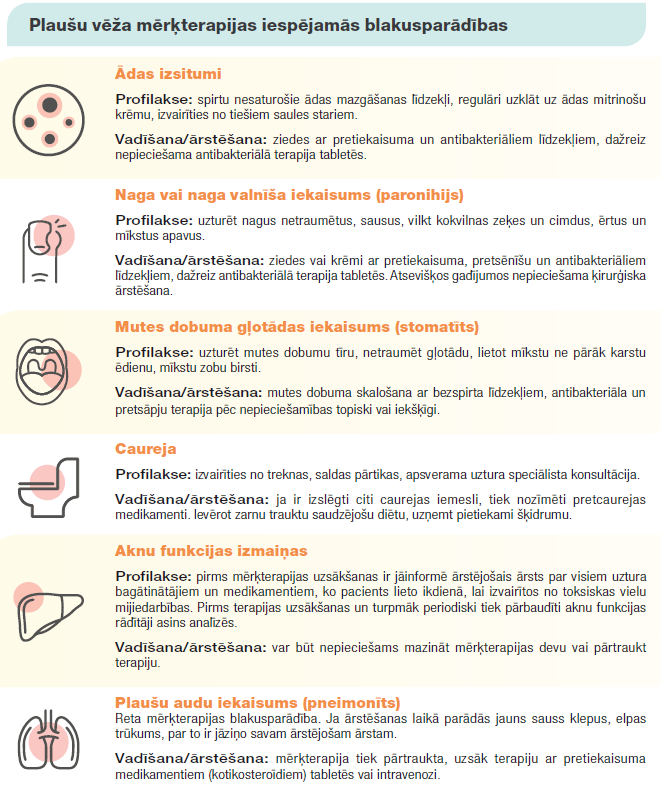

Mērķterapija

Ķīmijterapijas medikamentu blakusparādību profils un rezistence pret zālēm likusi pētniekiem meklēt arvien jaunas ārstēšanas pieejas. Mērķterapija ir medikamenti, kuri iedarbojas uz specifiskiem audzēja gēniem, proteīniem, augšanas faktoriem vai ietekmē audzēja vidi. Mērķterapijas preparātu klāsts kļūst aizvien plašāks, kas ļauj panākt efektīvāku un specifiskāku vēža terapiju. Tablešu forma atvieglo šīs terapijas pielietojumu.

Mērķterapijas preparāti bloķē noteiktu molekulu vai receptoru vēža šūnā. Lielāko daļu mērķterapijas nozīmē tikai, ja plaušu vēža audu parauga šūnās ir atrasta speciāla mutācija. Nesīkšūnu plaušu vēža terapijā lielākā mērķpreparātu grupa ir tirozīnkināzes inhibitori (TKI). Tirozīnkināzes ir enzīmi, kuri veselā organismā vajadzības gadījumā stimulē šūnas augšanu un dalīšanos. Līdz 15% nesīkšūnu plaušu vēža gadījumu (pārsvarā adenokarcinomās) notiek tirozīnkināžu receptoru gēnu bojājums, mutācija. Tas izraisa šūnas nekontrolētu augšanu un dalīšanos. Mutācijas biežāk tiek konstatētas pacientiem ar plaušu adenokarcinomu, sievietēm, nesmēķētājiem, aziātiem. Bloķējot bojātos receptorus ar mērķterapijas preparātiem, vēža šūnas zaudē spēju dalīties, audzējs pārstāj augt. Tādēļ audzēju paraugus ir nepieciešams testēt, lai atrastu katram pacientiem vispiemērotāko terapiju.

Līdzīgi kā citotoksiskās ķīmijterapijas medikamenti, arī mērķterapija var izraisīt blaknes – sliktu dūšu, vēdera izejas traucējumus, ādas un nagu izmaiņas, izmaiņas asins analīzēs. Atkarībā no izteiktības un ietekmes uz pacienta dzīves kvalitāti blaknes iedala smaguma pakāpēs. Blaknes ir ārstējamas un lielai daļai pacientu ārstēšana ar mērķterapiju norit bez izteiktām komplikācijām.

Atkarībā no smaguma pakāpes tiek noteikts, vai ir jāsamazina devas, vai mērķterapija ir jāpārtrauc. Mērķterapijas saņemšanas periodā ik pēc dažiem mēnešiem notiek kontroles vizītes pie ārstējošā onkologa ķīmijterapeita, tiek izvērtētas pacienta sūdzības un asins analīzes. Ja pacientam parādās kādas no blaknēm, par tām ir jāsazinās ar savu ārstējošu ārstu.